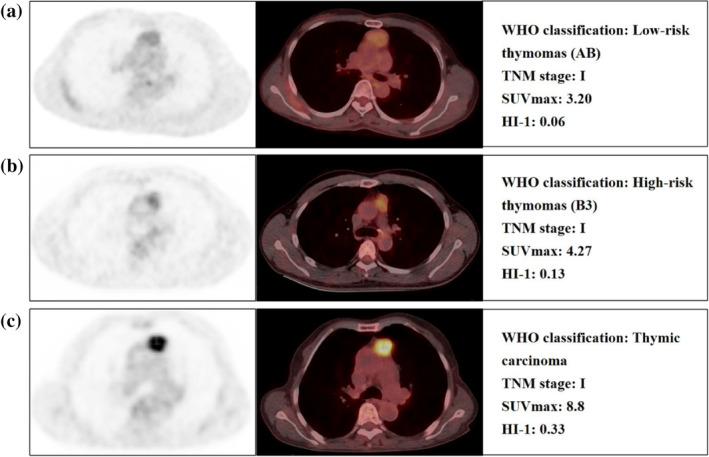

This retrospective study included 100 patients diagnosed with TETs who underwent pretreatment F-FDG PET/CT. The maximum and mean standardized uptake values (SUVmax and SUVmean), metabolic tumor volume (MTV), and total lesion glycolysis (TLG) on PET/CT were measured. Heterogeneity index-1 (HI-1; standard deviation [SD] divided by SUVmean) and heterogeneity index-2 (HI-2; linear regression slopes of the MTV according with different SUV thresholds), were evaluated as heterogeneity indices. Associations between these parameters and patient survival outcomes were analyzed.

The univariate analysis showed that Masaoka stage, TNM stage, WHO classification, SUVmax, SUVmean, TLG, and HI-1 were significant prognostic factors for progression-free survival (PFS), while MTV, HI-2, age, gender, presence of myasthenia gravis, and maximum tumor diameter were not. Subsequently, multivariate analyses showed that HI-1 (p < 0.001) and TNM stage (p = 0.002) were independent prognostic factors for PFS. For the overall survival analysis, TNM stage, WHO classification, SUVmax, and HI-1 were significant prognostic factors in the univariate analysis, while TNM stage remained an independent prognostic factor in multivariate analyses (p = 0.024). The Kaplan Meier survival analyses showed worse prognoses for patients with TNM stages III and IV and HI-1 ≥ 0.16 compared to those with stages I and II and HI-1 < 0.16 (log-rank p < 0.001).